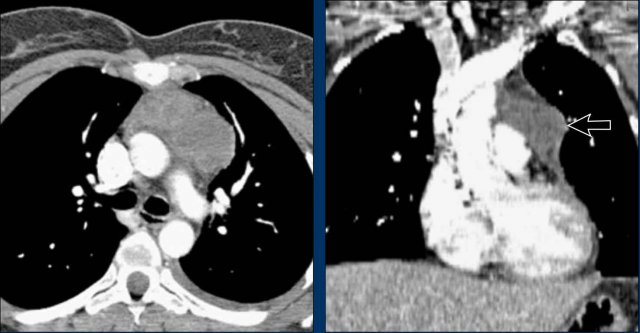

Case Example 2 - CT imaging

- CT imaging revealed a large posterior pericardial effusion compressing the left ventricle (blue arrow: effusion; red arrow: compressed, contrast-filled left ventricle).

- Surgical exploration confirmed a large posterior pericardial hematoma.

Note: Minimal anterior fluid on ultrasound may underestimate the true volume if the effusion is loculated posteriorly, highlighting the value of CT in postoperative cases.